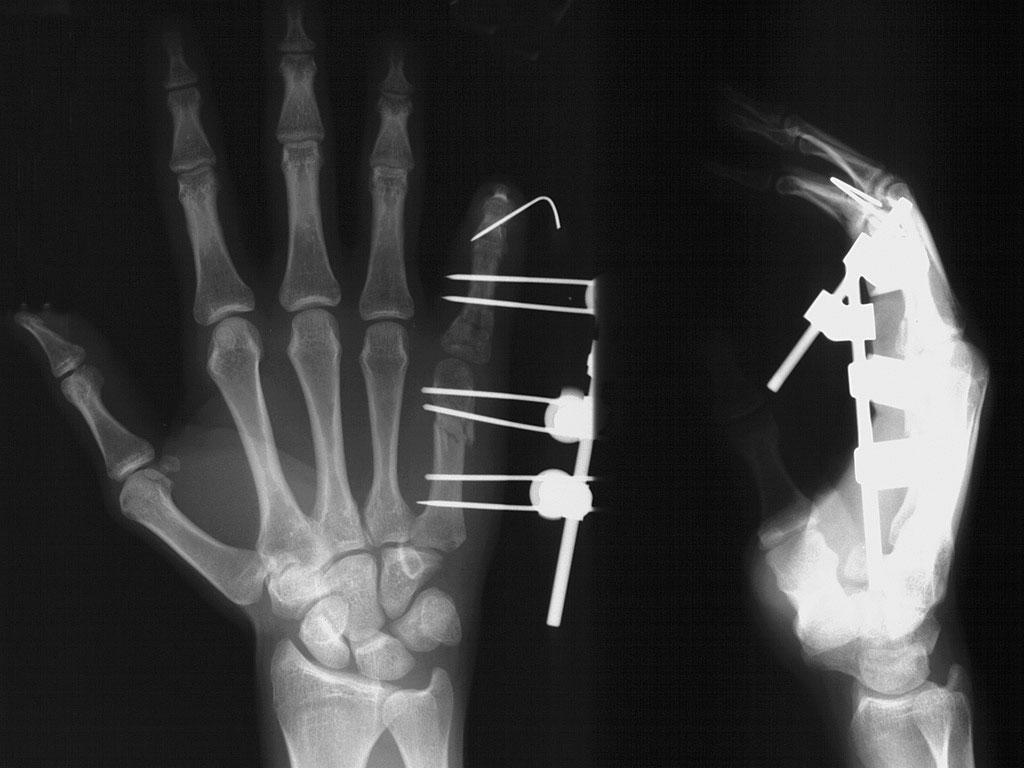

From www.vrogue.co

Wrist External Fixation System Fixus33 Fixus Humerus vrogue.co What Is External Fixation Used For External fixation facilitates external bridging callus. An external fixator is a stabilizing frame to hold the broken bones in proper position. What is an external fixator? “classic” hybrid fixation has no role in current orthopaedic practice (poor biomechanics) current “hybrid fixation” involves multiplanar fixation with a combination of. An external fixator is a frame made of metal that keeps your. What Is External Fixation Used For.